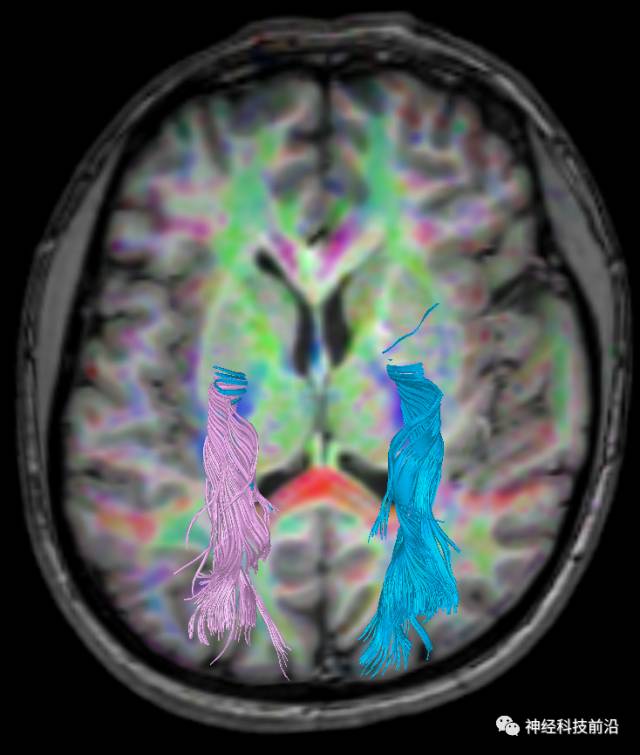

下面为皮质脊髓束的走形及位置

下面为皮质脑桥束的走形方位

皮质脊髓束与皮质脑桥束的关系毗邻

上述纤维束与小脑中脚的位置毗邻